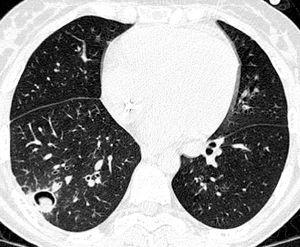

Período intermedio

En este período el microorganismo más importante es el CMV. Por ello debe hacerse énfasis en las medidas profilácticas anteriormente descritas. El tratamiento preventivo ha sido uno de los grandes avances en este campo y consiste en el tratamiento de la infección, detectada por antigenemia o PCR en sangre o en LBA, con ganciclovir o foscarnet antes de que aparezca enfermedad. Si se desarrolla una neumonía intersticial por CMV (fig. 4) el tratamiento con ganciclovir asociado a inmunoglobulinas permitirá su control en el 30-50% de los casos. También en este período aparecen infecciones fúngicas. Aunque no es objetivo de esta monografía el extenderse en el tratamiento de estas infecciones, únicamente señalar que el tratamiento inicial de la aspergilosis invasora es voriconazol y el de la candidiasis puede ser caspofungina o anfotericina B (o sus formulaciones) y una vez conocida la especie, si es sensible a fluconazol se puede continuar con dicho agente.

Figura 4. Neumonía intersticial por CMV.